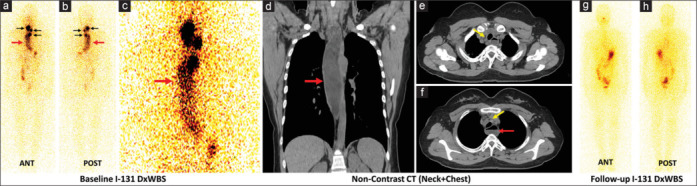

We present the case of a 36-year-old woman with papillary thyroid cancer (PTC) who had undergone thyroidectomy and nodal dissection. In addition to thyroid remnant and nodal metastases, initial postoperative radioiodine (RAI) diagnostic whole-body scintigraphy showed abnormal diffusely increased linear band-like uptake in the thorax corresponding to the esophageal contour, raising suspicion of lower esophageal obstruction. Retrospective inquiry revealed a history of long-standing, progressive dysphagia. Findings of computed tomography, barium swallow study, and esophageal manometry were consistent with achalasia cardia. She underwent high-dose RAI therapy for PTC and laparoscopic cardio-myotomy for achalasia cardia. This case report aims to familiarize nuclear medicine physicians with the appearance of achalasia cardia on RAI scintigraphy, which may mask surrounding lymph nodal or vertebral metastases. Such a finding when encountered should also prompt further work-up and appropriate management.